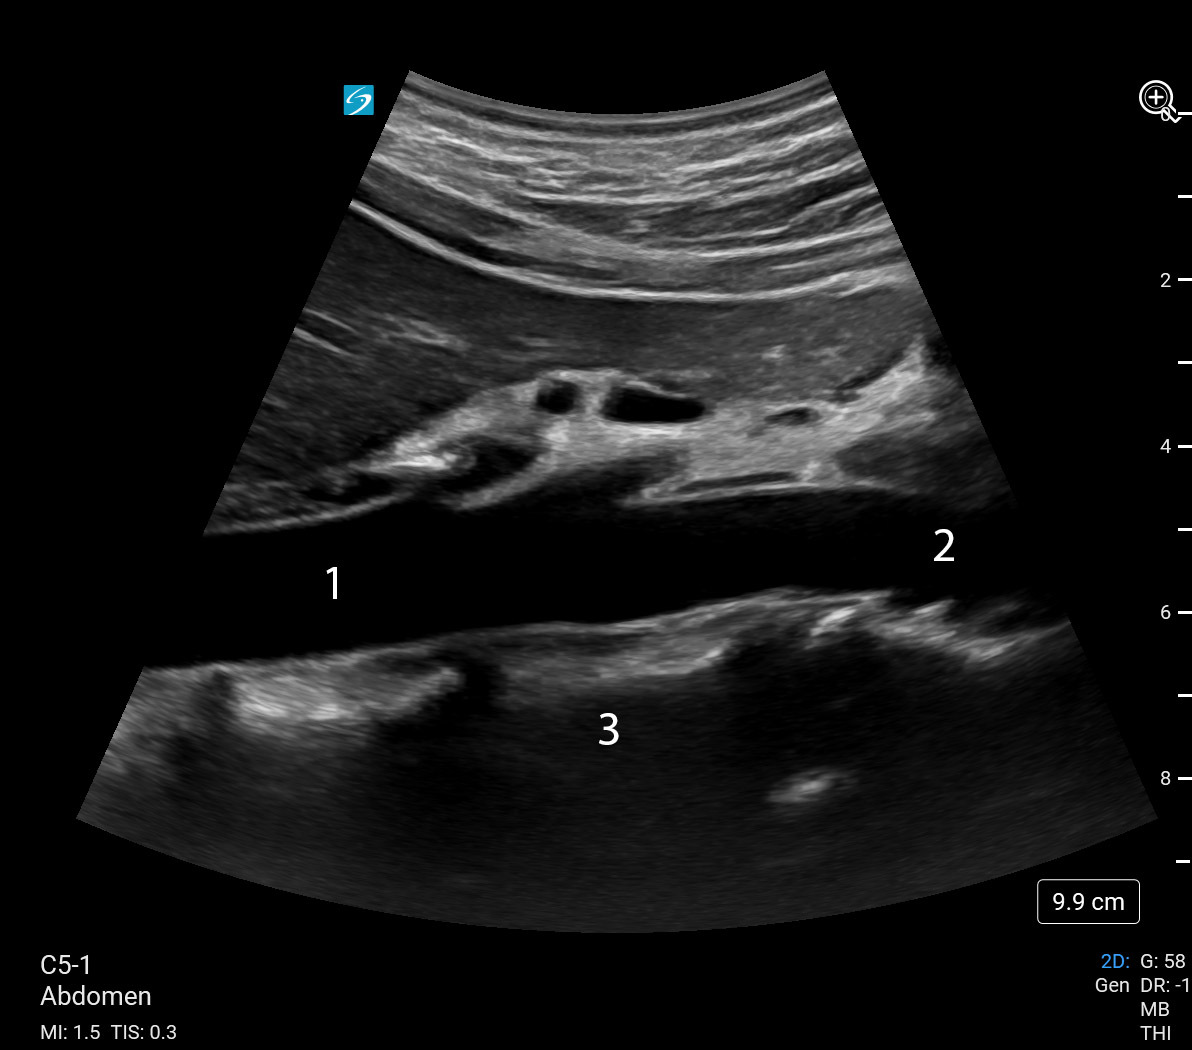

Bild: Mitt. distale Aorta, sagittal/longitudinal

Aorta, Mitte

Aorta, distal

Wirbelsäule